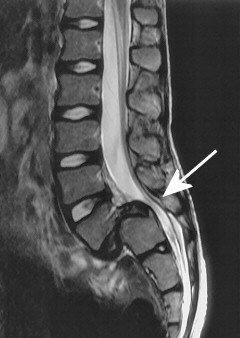

它很容易因長期姿勢不良或腰椎負重過重而造成破裂或突出,進而壓迫到腰部的神經,導致受傷部位疼痛、麻木或下肢麻痺疼痛。其好發部位為腰椎第四節與第五節或第五節與薦椎之間(即L4-5與L5-S1)。而容易發生的年齡有二個階段︰一個是在20--30歲之間,另一個則是40--50歲之間。